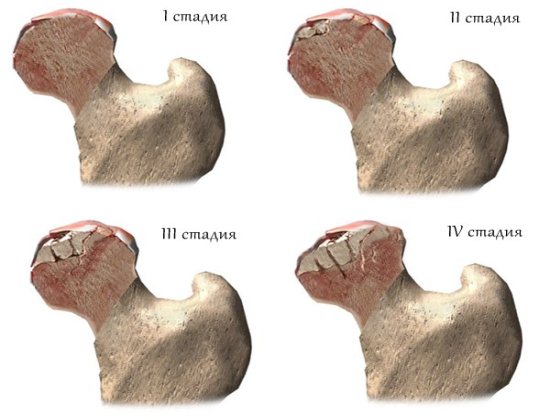

- аваскулярный (асептический) некроз головки бедра

- остеохондропатии (зачастую приводят к микропереломам)